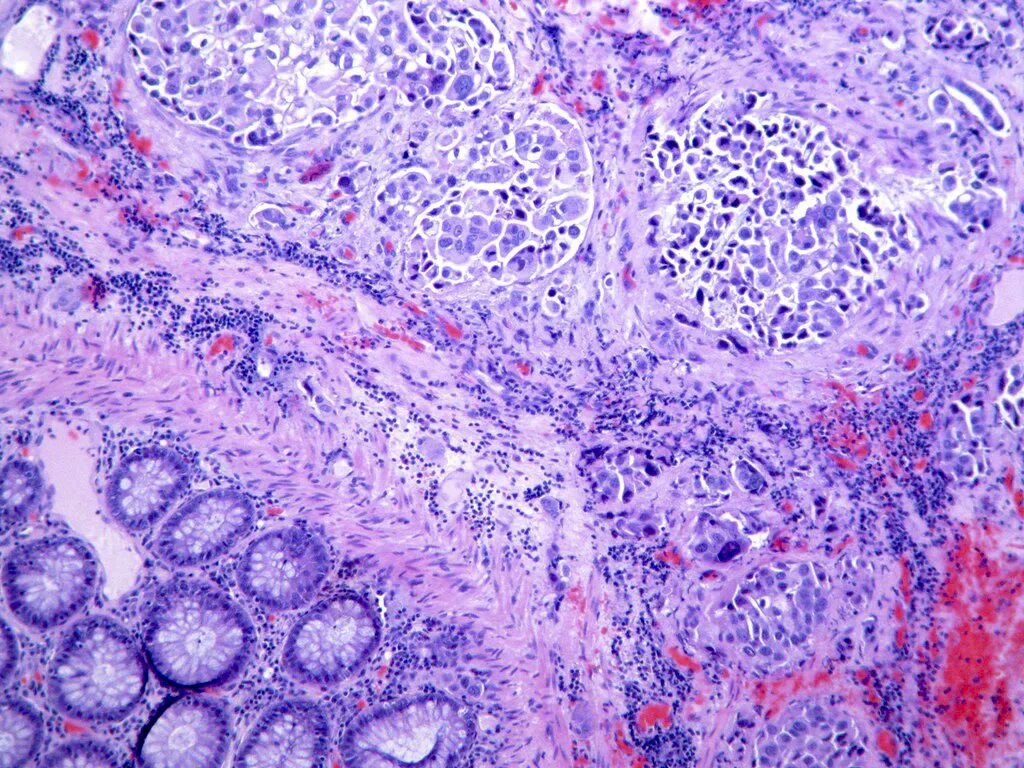

Гистология фото